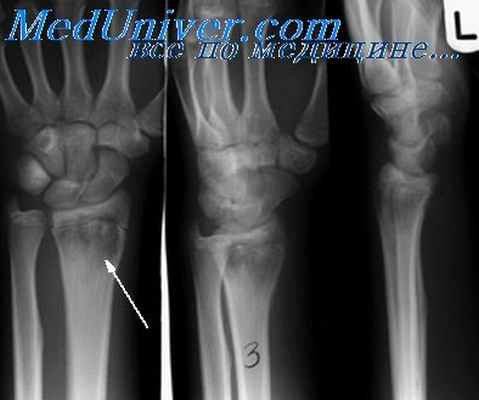

- Рентгеновский

1. «Остеомиелит 1-го MTP» Джеймс Хейлман, доктор медицины - (CC BY-SA 4.0) через Commons Wikimedia

2. «SepticArth2011 (обрезано)» Тетсуо Хагино, Масанори Вако, Сатоши Очиаи - (CC BY 2.5) через Commons Wikimedia

Остеомиелит

Бактерии могут проникать в кости из-за травмы, операции или в результате инфекции мягких тканей и крови. Возникший из-за этого остеомиелит может проявляться остро, подостро или хронически болью в костях, лихорадкой и лейкоцитозом. У пациентов с серповидно-клеточной анемией риск остеомиелита в 100 раз выше. На рентгеновских снимках можно увидеть разрушение костного вещества из-за отслоения надкостницы. Может образоваться абсцесс или свищ. Исследование костей с помощью рентгена или ультразвука — самое важное первичное обследование для определения остеомиелита у взрослых и детей. Диагноз часто устанавливают поздно, поэтому важно вовремя делать снимки. Лечение включает: